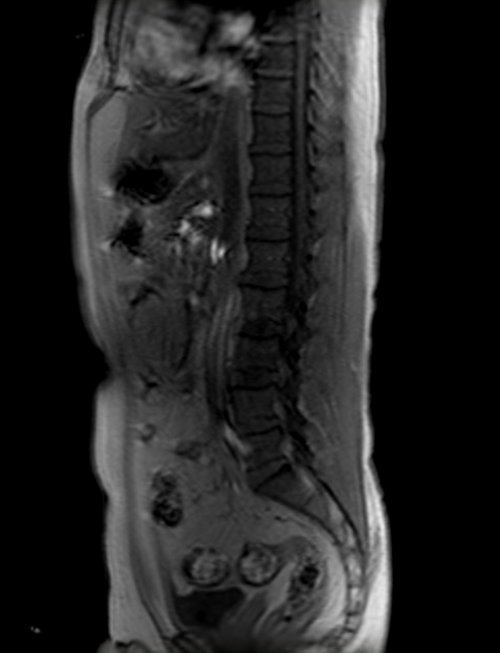

mra abdomen localizer 1 - MRI